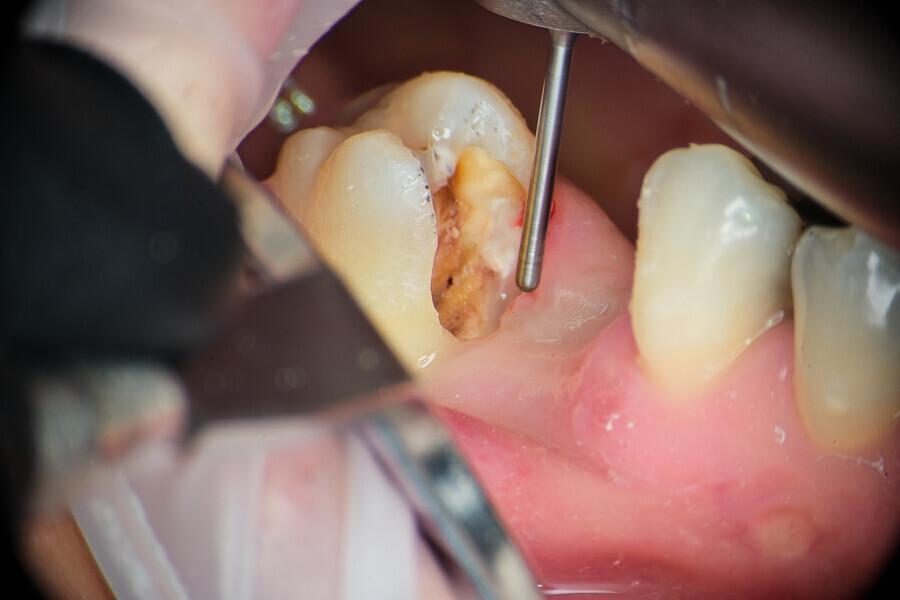

Case 3

A 34-year-old patient was referred to our clinic for endodontic primary treatment. The patient had acute pain and was treated during an emergency visit. The initial radiograph (Fig. 26) and intra-oral examination demonstrated the need for endodontic intervention for tooth #16. The access cavity was created with the use of the ED3D ultrasonic scaler tip (Woodpecker) and adapted in order to visualise all of the pulp chamber floor (Fig. 27). A pulp stone was located and removed also with the ED3D tip (Figs. 28 & 29). Before instrumentation, initial irrigation of the cavity with 5.25% sodium hypochlorite and activation with EDDY tips was performed in order to remove remnants of the pulp from the pulp chamber (Fig. 30). The initial glide path was then created using manual ISO #8–10 K-files (VDW). Mechanical instrumentation with VDW.ROTATE files in the second mesiobuccal, first and second distobuccal, and palatal canals and the R25 RECIPROC blue file (VDW) was used in the first mesiobuccal canal (Fig. 31). All instruments were used in the in–out technique with copious irrigation with activation in between instruments. Owing to the very long and curved canals, the IrriFlex needle (PD) was used for the final irrigation protocol (Fig. 32). Obturation was done with VDW.1Seal using the cavit piston technique (Fig. 33). The final radiograph was taken and examined regarding the clinical outcome (Fig. 34). From the visible lateral anatomy obturation, it can be concluded that the in–out technique for use during preparation is a promising solution for clinical success in canal preparation.